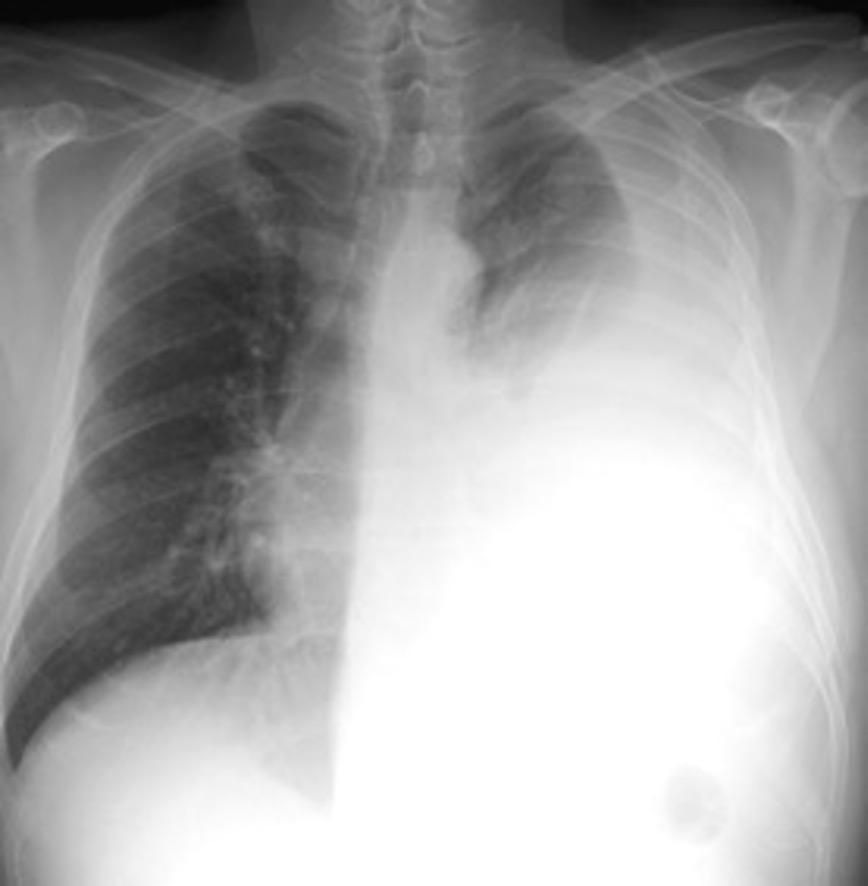

Marzo 2014: Perforación longitudinal distal secundaria a episodio de vómito (síndrome de Boerhaave). Derrame pleural izdo. que evoluciona a empiema.

Wang C-T et al. Tension hydropneumothorax in a Boerhaave syndrome patient: A case report . World J Emerg Med, 2021. Katabathina V et al. Nonvascular, nontraumatic mediastinal emergencies in adults:a comprehensive review of imaging findings. Radiographics. 2011.